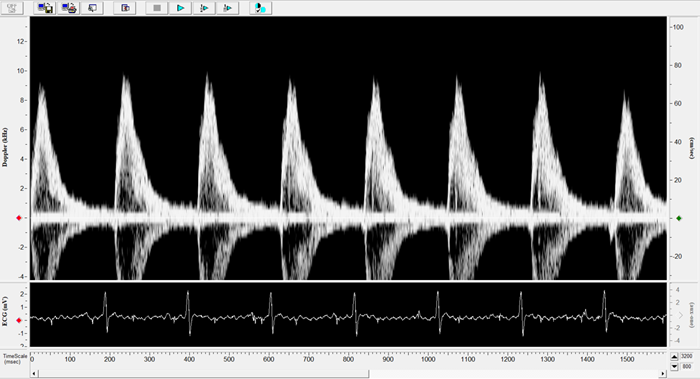

Imaging gallery - Doppler Flow Velocity System

Carotid Image. Image Credit: Scintica Instrumentation Inc.